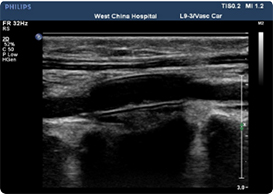

超声检测结果

REVOVAS®植入恒河猴后4周, 干细胞实现血管内膜层再生。